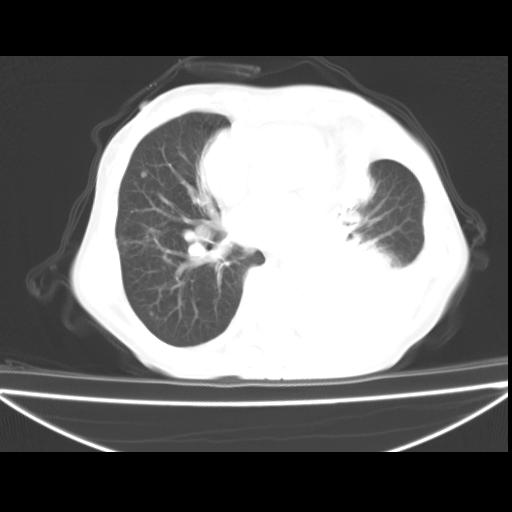

以下是引用zxl51642在2010-3-24 18:49:00的发言:[br]结合乳腺癌术后病史,考虑双肺及纵隔淋巴结多发转移、左侧胸膜转移并左侧大量胸水、左下肺膨胀不全。